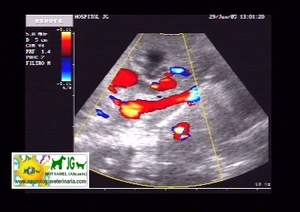

La ecografía abdominal en el diagnóstico de enfermedades neurológicas. |